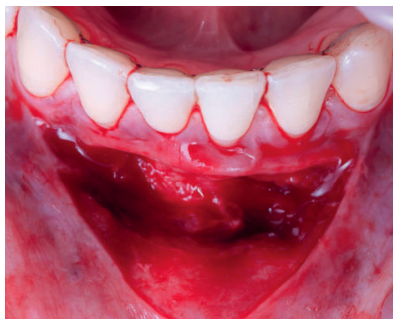

Previamente a la intervención, la paciente se enjuagó durante 1 minuto con un colutorio de clorhexidina. La técnica quirúrgica comenzó con la preparación del lecho receptor, para ello se realizó una incisión sulcular a espesor parcial a nivel de la recesión, se continúo diseccionando apical y lateralmente, extendiéndose de 3 a 5 mm de la recesión para permitir la entrada del ITC y su estabilización. Posteriormente, se realizó una incisión en el fondo de vestíbulo, dejando un puente de tejido que servirá para un doble aporte sanguíneo al injerto (Figura 2).

Previamente a la intervención, la paciente se enjuagó durante un minuto con un colutorio de clorhexidina. La técnica quirúrgica comenzó con la preparación del lecho receptor, se realizaron incisiones intrasulculares a nivel cervical hasta la línea ángulo de todos los dientes del frente antero-inferior (33-43), desinsertando la base de la papila sin seccionarla con la ayuda de instrumentos de tunelización. Posteriormente se realizó una incisión en el fondo de vestíbulo (Figura 11). A continuación, se obtuvo un injerto de tejido conectivo del paladar introduciéndolo en el lecho receptor, siendo todas las suturas realizadas de la misma manera que en el caso clínico 1, usando tanto material reabsorbible como no reabsorbible de 5/0 y 6/0 ceros (Figura 12).